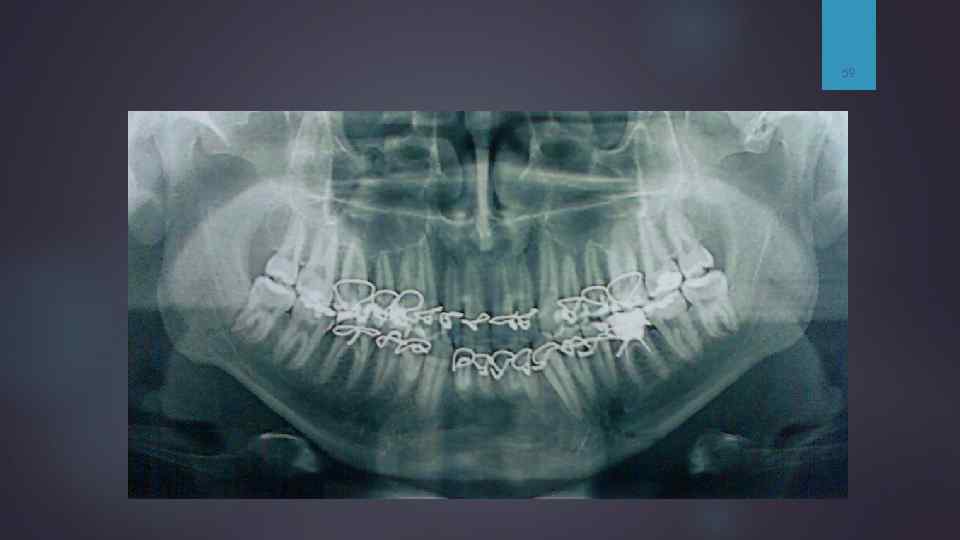

Перелом нижней челюсти 53 Зубы иммобилизированы проволокой (шинирование). На рентгенограмме черепа в носо-подбородочной проекции определяются нарушение целостности костной ткани нижней челюсти в области тела (подбородочного отверстия) слева с четкими неровными, мелко зазубренными контурами на уровне зуба 3. 2 шириной до 3 -4 мм, а также отмечается нарушение целостность стенки лунки 3. 2 зуба. Аналогичное нарушение целостности нижней челюсти отмечается справа в области угла нижней челюсти шириной до 4 мм в нижнем отделе и до 6 мм в верхнем, с нарушением целостности стенки лунки зуба 4. 7. В области нижнечелюстной вырезки справа отмечается нарушение костной структуры с формированием осколков в виде венечного и мыщелкого отросков. Заключение: шинирование. Множественные переломы нижней челюсти. Фиксация неудовлетворительная. Рекомендована МСКТ черепа для определения характера повреждения в области ВНЧС справа (расхождения отломков, наличия осколков).